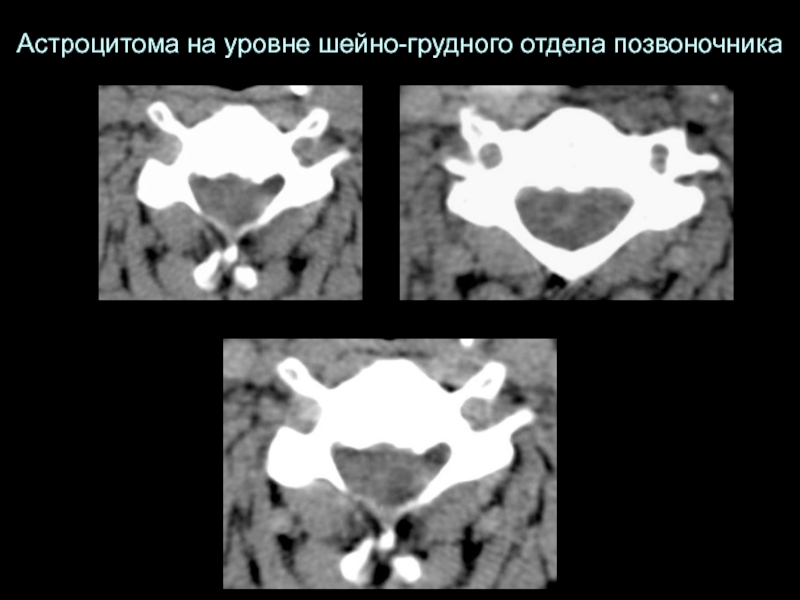

Слайд 22Астроцитома на уровне шейно-грудного отдела позвоночника

Астроцитома на уровне шейно-грудного отдела позвоночника